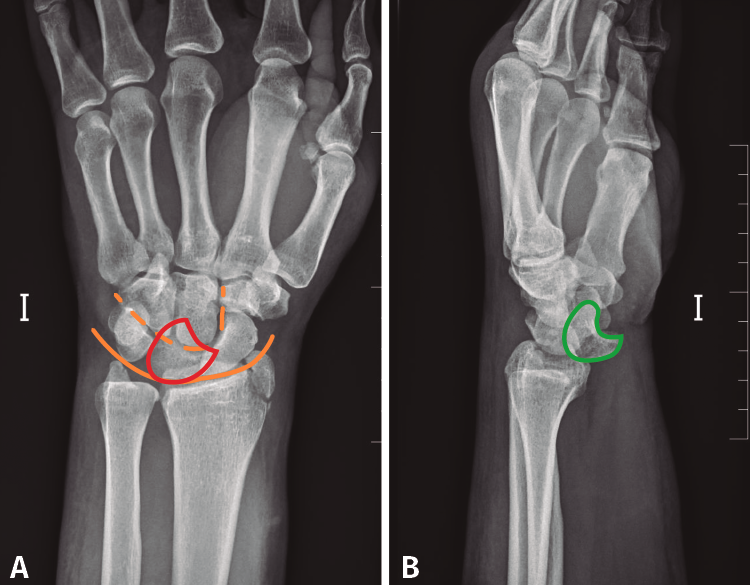

Desde el Servicio de Urgencias se solicita un radiografía anteroposterior y oblicua de mano, muñeca y tercio distal del antebrazo izquierdo. Si observamos detenidamente la radiografía anteroposterior, se observa una alteración en los arcos de Gilula y una posición alterada del semilunar (flexión palmar). Debido a que estas radiografías no son las más adecuadas para el estudio de la muñeca, podría pasar desapercibida la lesión (Figura 1).

Figura 1. Radiografía (A) anteroposterior y (B) radiografía oblicua de mano, muñeca y tercio distal del antebrazo realizadas durante la atención en urgencias inicial. Se observa la fractura de la estiloides radial (flecha). Alteración en los arcos de Gilula (línea). Alteración en la forma del semilunar, en flexión volar (rojo).

Se solicitó una radiografía anteroposterior y lateral pura de muñeca izquierda, en la que se observa una luxación transestiloperilunar (Figura 2).

Figura 2. A: radiografía anteroposterior en la que se observa la disrupción de los arcos de Gilula. Semilunar en flexión volar (rojo); B: radiografía lateral pura de muñeca en la que se observa la pérdida de la congruencia semilunar, hueso grande y 3.er metatarsiano (verde).